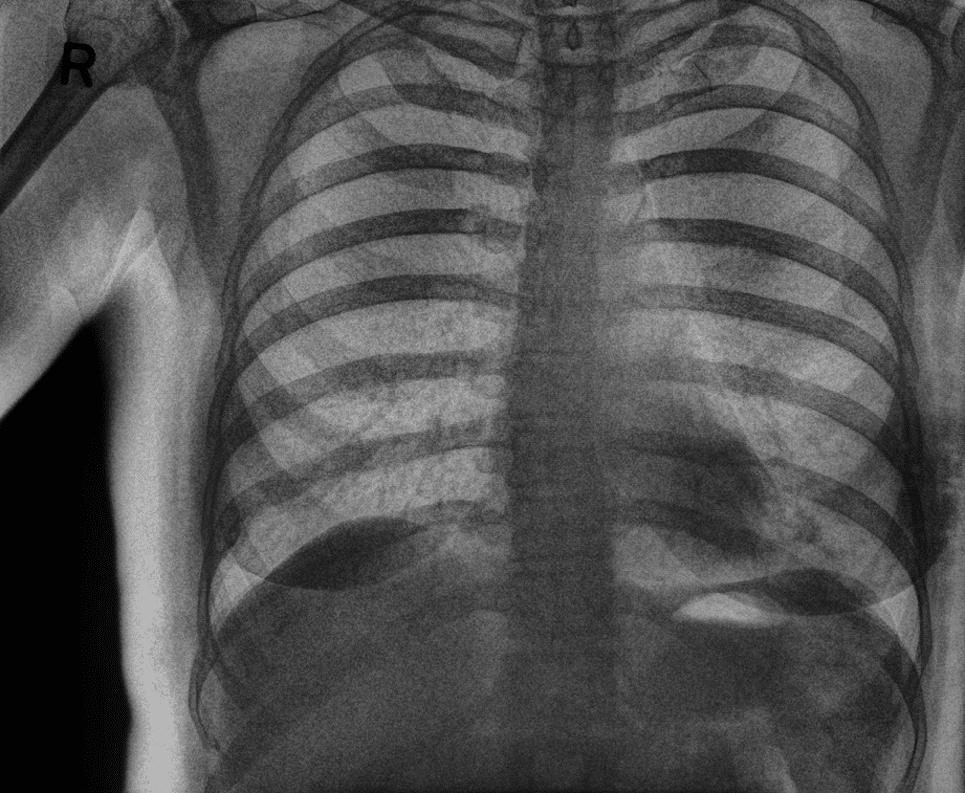

Rib and Skeletal Trauma

In this case, the conventional DR image shows subtle findings. The spectral soft-tissue image reduces overlying bone, making the pneumothorax more conspicuous. The corresponding bone-selective image highlights a rib fracture, a potential underlying cause of the pneumothorax.